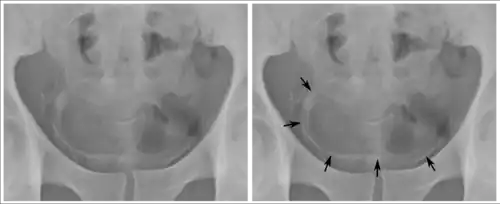

Inflammation and infection

Calcifications on bladder wall caused by urinary schistosomiasis

Cystitis refers to infection or inflammation of the bladder. It commonly occurs as part of a urinary tract infection.[25] In adults, it is more common in women than men, owing to a shorter urethra. It is common in males during childhood, and in older men where an enlarged prostate may cause urinary retention.[25] Other risk factors include other causes of blockage or narrowing, such as prostate cancer or the presence of vesico-ureteric reflux; the presence of outside structures in the urinary tract, such as urinary catheters; and neurologic problems that make passing urine difficult.[25] Infections that involve the bladder can cause pain in the lower abdomen (above the pubic symphysis, so called "suprapubic" pain), particularly before and after passing urine, and a desire to pass urine frequently and with little warning (urinary urgency).[25] Infections are usually due to bacteria, of which the most common is E coli.[25]